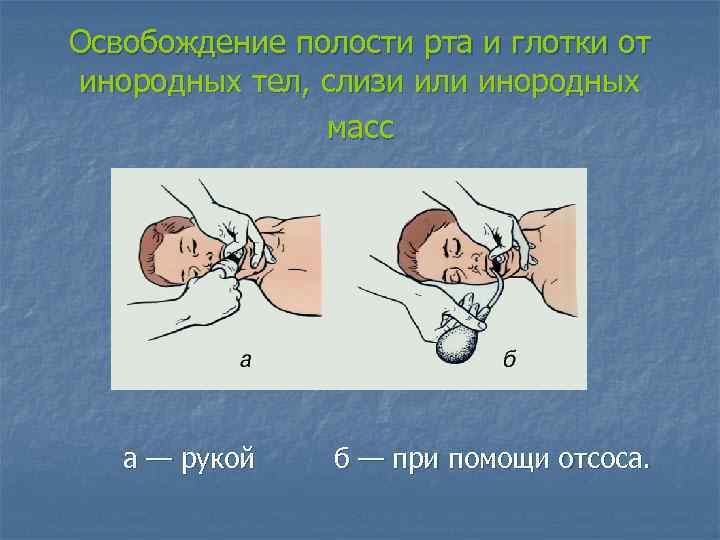

Освобождение полости рта и глотки от инородных тел, слизи или инородных масс а — рукой б — при помощи отсоса.